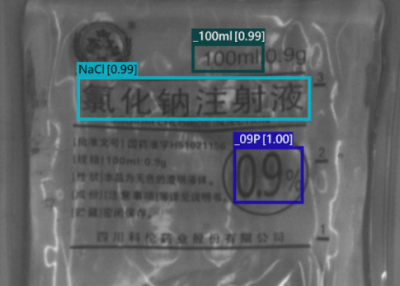

With SolVision‘s segmentation tool, various labels can be identified from sample images to train a visual inspection system capable of classifying information on IV bags based on their distinctive features. SolVision’s advanced AI-based technology is also unaffected by transparent objects, label complexity, or appearance.

Sodium Chloride Solution